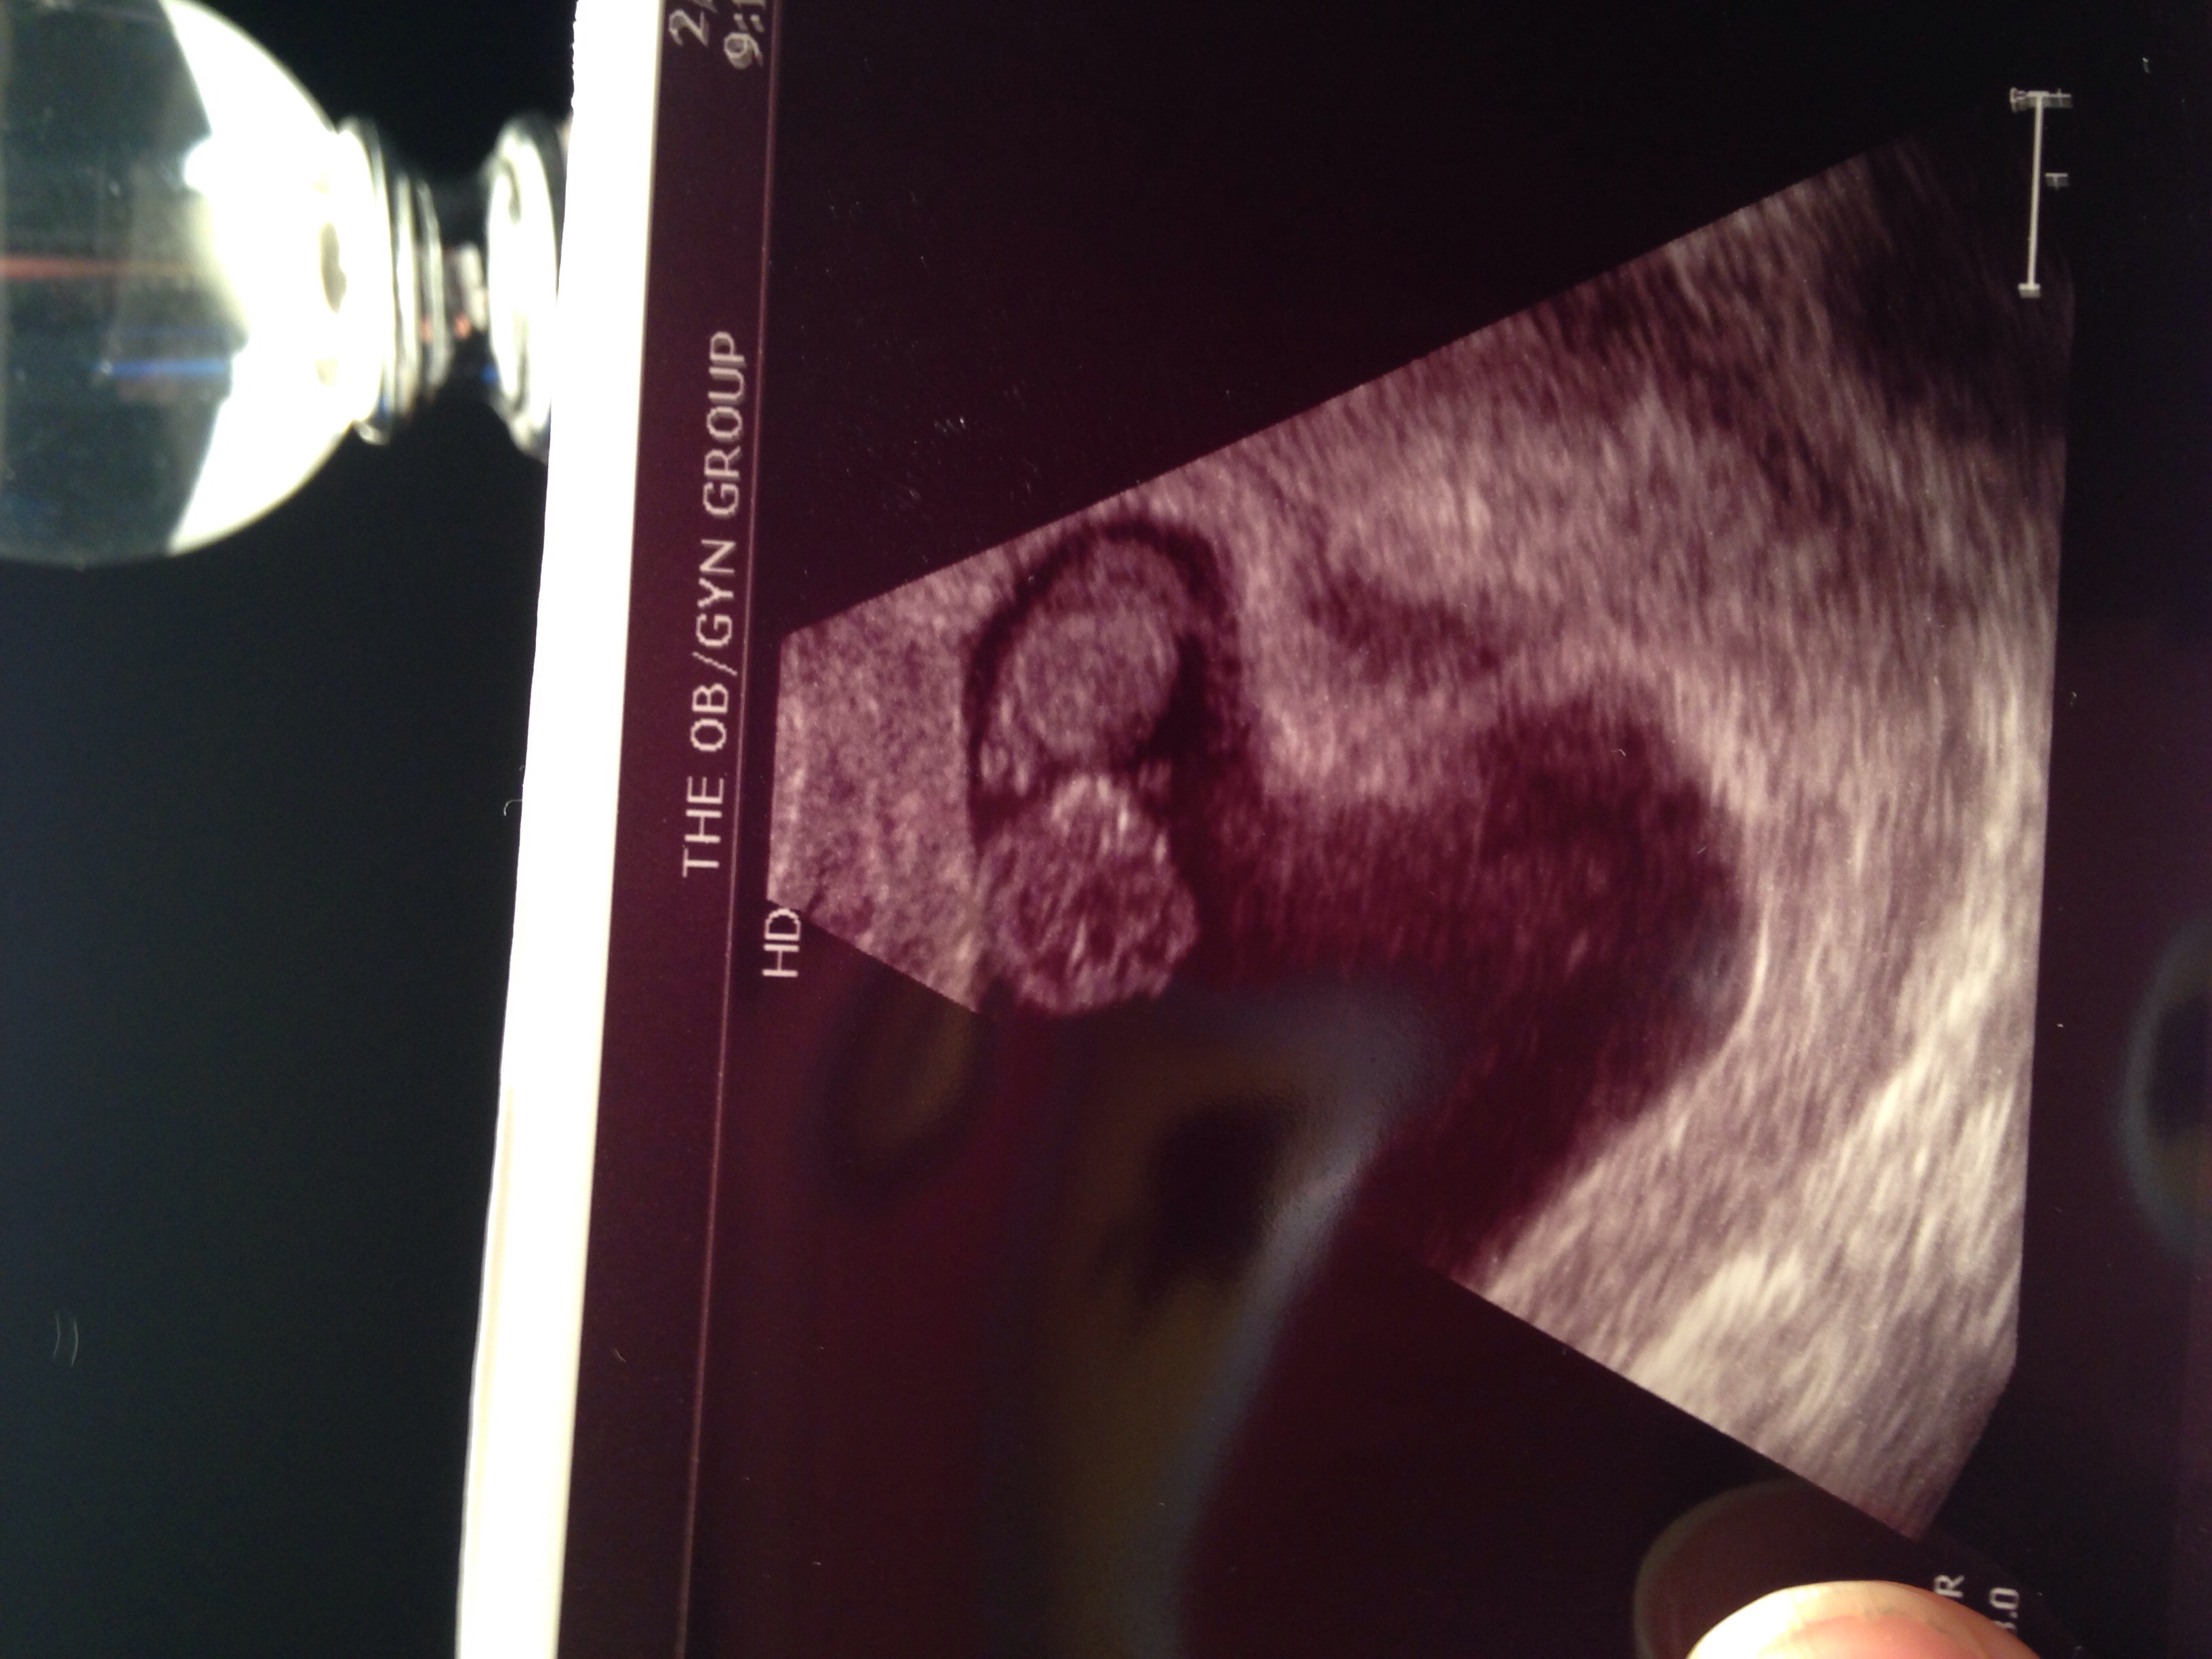

So jealous of that great photo! Our first and only ultrasound photo so far was right at 10 weeks but our photo is kind of blurry. 10 weeks is supposed to be the size of a prune and our baby definitely looks more like a prune than it does a baby in our ultrasound. Haha. Lets hope baby gets cuter with age.